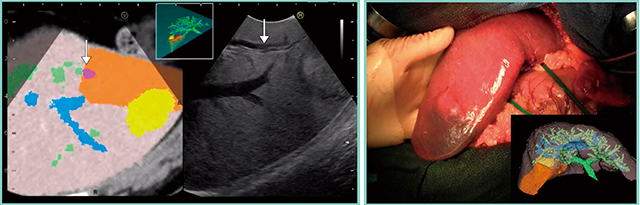

症例1は,臓側面から後下区門脈枝(P6)を穿刺染色して系統的切除を行った肝細胞がん症例である。臓側面からはP6のオリエンテーションをつけづらいことがあるが,RVSの画像を参照しながら穿刺染色を行ったところ,ほぼ術前のシミュレーションどおりの位置を染色することができた(図2)。

図2 症例1:臓側面からP6(↓)を穿刺染色して系統的切除を行った肝細胞がん症例